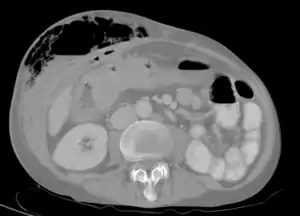

| Abdominal CT scan with right colocutaneous fistula and associated subcutaneous pneumatosis | |